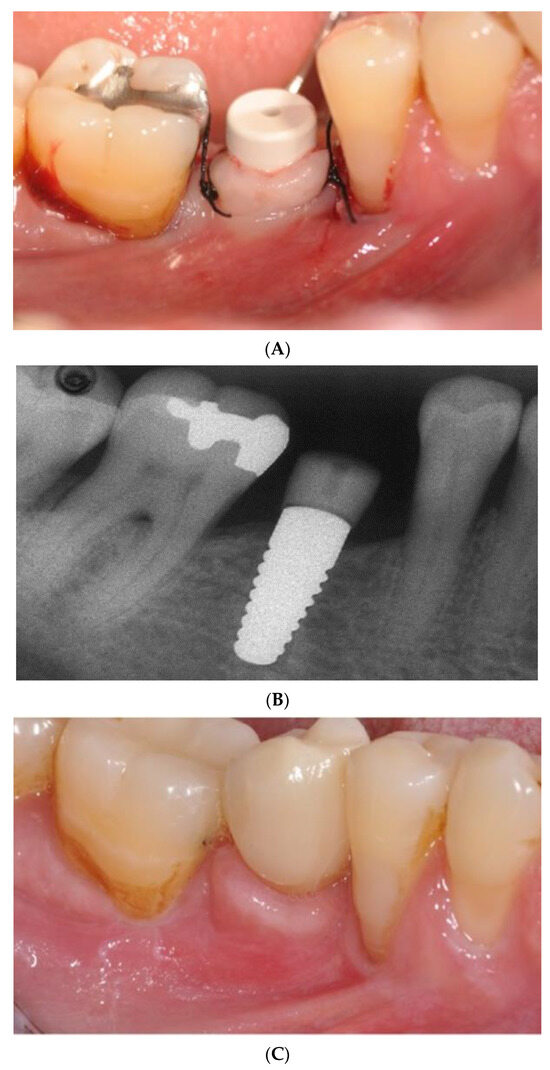

- Pirker, W.; Kocher, A. Immediate, non-submerged, root-analogue zirconia implant in single tooth replacement. Int. J. Oral Maxillofac. Surg. 2008, 37, 293–295. [Google Scholar] [CrossRef]

- Pirker, W.; Kocher, A. Immediate, non-submerged, root-analogue zirconia implants placed into single-rooted extraction sockets: 2-year follow-up of a clinical study. Int. J. Oral Maxillofac. Surg. 2009, 38, 1127–1132. [Google Scholar] [CrossRef]

- Pessanha-Andrade, M.; Sordi, M.B.; Henriques, B.; Silva, F.S.; Teughels, W.; Souza, J.C.M. Custom-made root-analogue zirconia implants: A scoping review on mechanical and biological benefits. J. Biomed. Mater. Res. B Appl. Biomater. 2018, 106, 2888–2900. [Google Scholar] [CrossRef]

- Pirker, W.; Wiedemann, D.; Lidauer, A.; Kocher, A.A. Immediate, single stage, truly anatomic zirconia implant in lower molar replacement: A case report with 2.5 years follow-up. Int. J. Oral Maxillofac. Surg. 2011, 40, 212–216. [Google Scholar] [CrossRef]

- Van Dooren, E.; Calamita, M.; Calgaro, M.; Coachman, C.; Ferencz, J.L.; Pinho, C.; Silva, N.R. Mechanical, biological and clinical aspects of zirconia implants. Eur. J. Esthet. Dent. 2012, 7, 396–417. [Google Scholar] [PubMed]

- Regish, K.M.; Sharma, D.; Prithviraj, D.R. An overview of immediate root analogue zirconia implants. J. Oral Implantol. 2013, 39, 225–233. [Google Scholar] [CrossRef] [PubMed]

- Mangano, F.G.; De Franco, M.; Caprioglio, A.; Macchi, A.; Piattelli, A.; Mangano, C. Immediate, non-submerged, root-analogue direct laser metal sintering (DLMS) implants: A 1-year prospective study on 15 patients. Lasers Med. Sci. 2014, 29, 1321–1328. [Google Scholar] [CrossRef]

- Akkoyun, E.F.; Demirbas, A.E.; Gumus, H.O.; Alkan, B.A.; Alkan, A. Custom-made root analog immediate dental implants: A prospective clinical study with 1-year follow-up. Int. J. Oral Maxillofac. Implants 2022, 37, 1223–1231. [Google Scholar] [CrossRef]